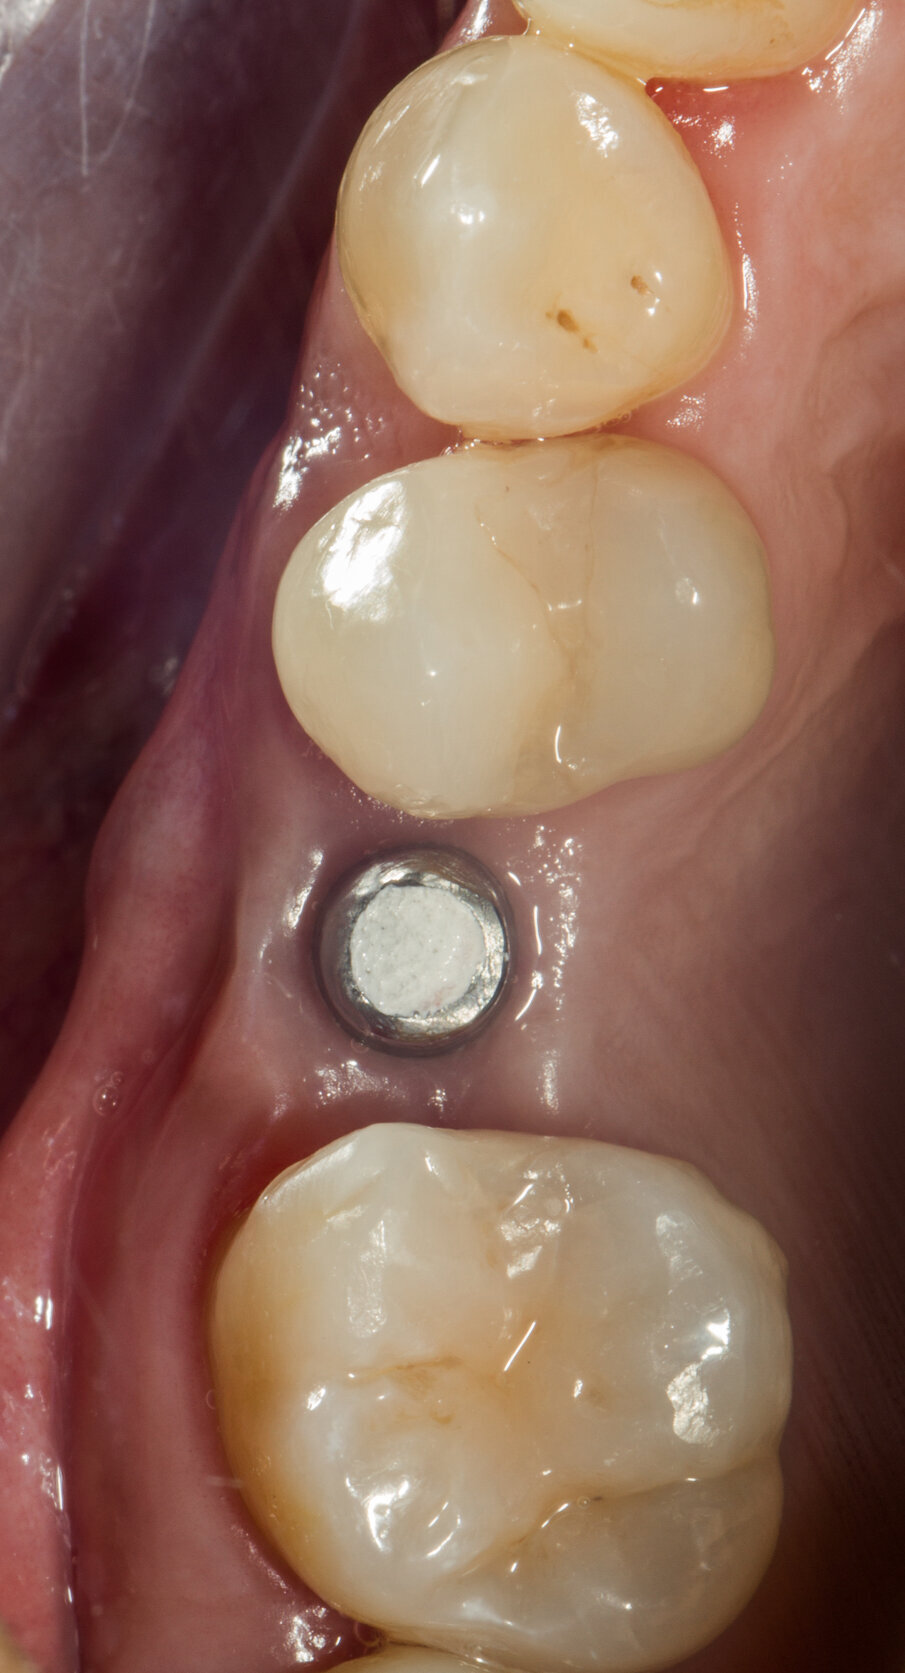

Viene inserito nel centro della cresta neoformata un impianto osteointegrato Neoss Tapered 4.0 x 13 mm con torque di inserimento di 60 Ncm e ISQ 80 (Figg. 22-24). La rigenerazione ossea crestale permette di inserire l’impianto in una posizione protesicamente guidata e con 2 mm di tessuto osseo vestibolare; questa situazione migliora la prevedibilità della riabilitazione implanto-protesica29-33. Dopo 2 mesi di provvisorizzazione si cementa il manufatto protesico definitivo (Figg. 25-28). Il controllo clinico e radiologico a 6 anni (Figg. 29, 30) mostra la stabilità dei tessuti molli e dell’osso perimplantare. Il confronto tra baseline e 6 anni dalla riabilitazione protesica evidenzia la stabilità nel tempo della rigenerazione volumetrica crestale (Fig. 31).

Fig. 22 - Impianto Neoss inserito al centro della cresta ossea.

Fig. 26 - Vista occlusale prima della cementazione del manufatto protesico.

Fig. 27 - Corona protesica definitiva cementata.

Fig. 28 - Corona protesica cementata; vista occlusale.